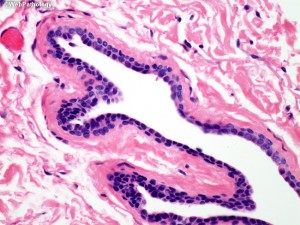

Eccrine hidrocystoma